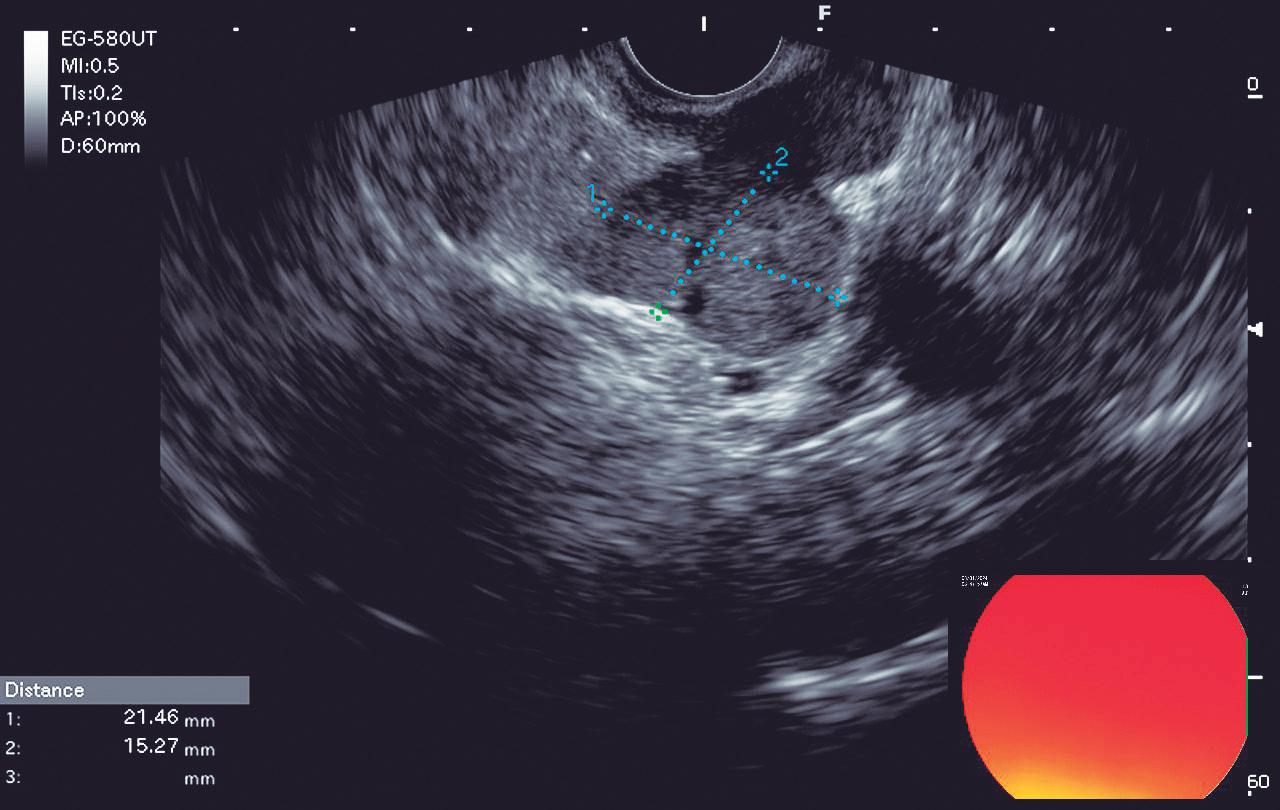

CASOS CLÍNICOS Biopsia guiada por ecoendoscopía como herramienta diagnóstica mínimamente invasiva para metástasis mesorrectal de carcinoma de células claras renales: reporte de caso

Nicole Marie Kahn, Mayra Florencia Defanti, Yanina Gabriela Carlino

CASE REPORTS Endoscopic Ultrasound-Guided Biopsy as a Minimally Invasive Diagnostic Tool for Mesorectal Metastasis From Clear Cell Renal Carcinoma: A Case Report